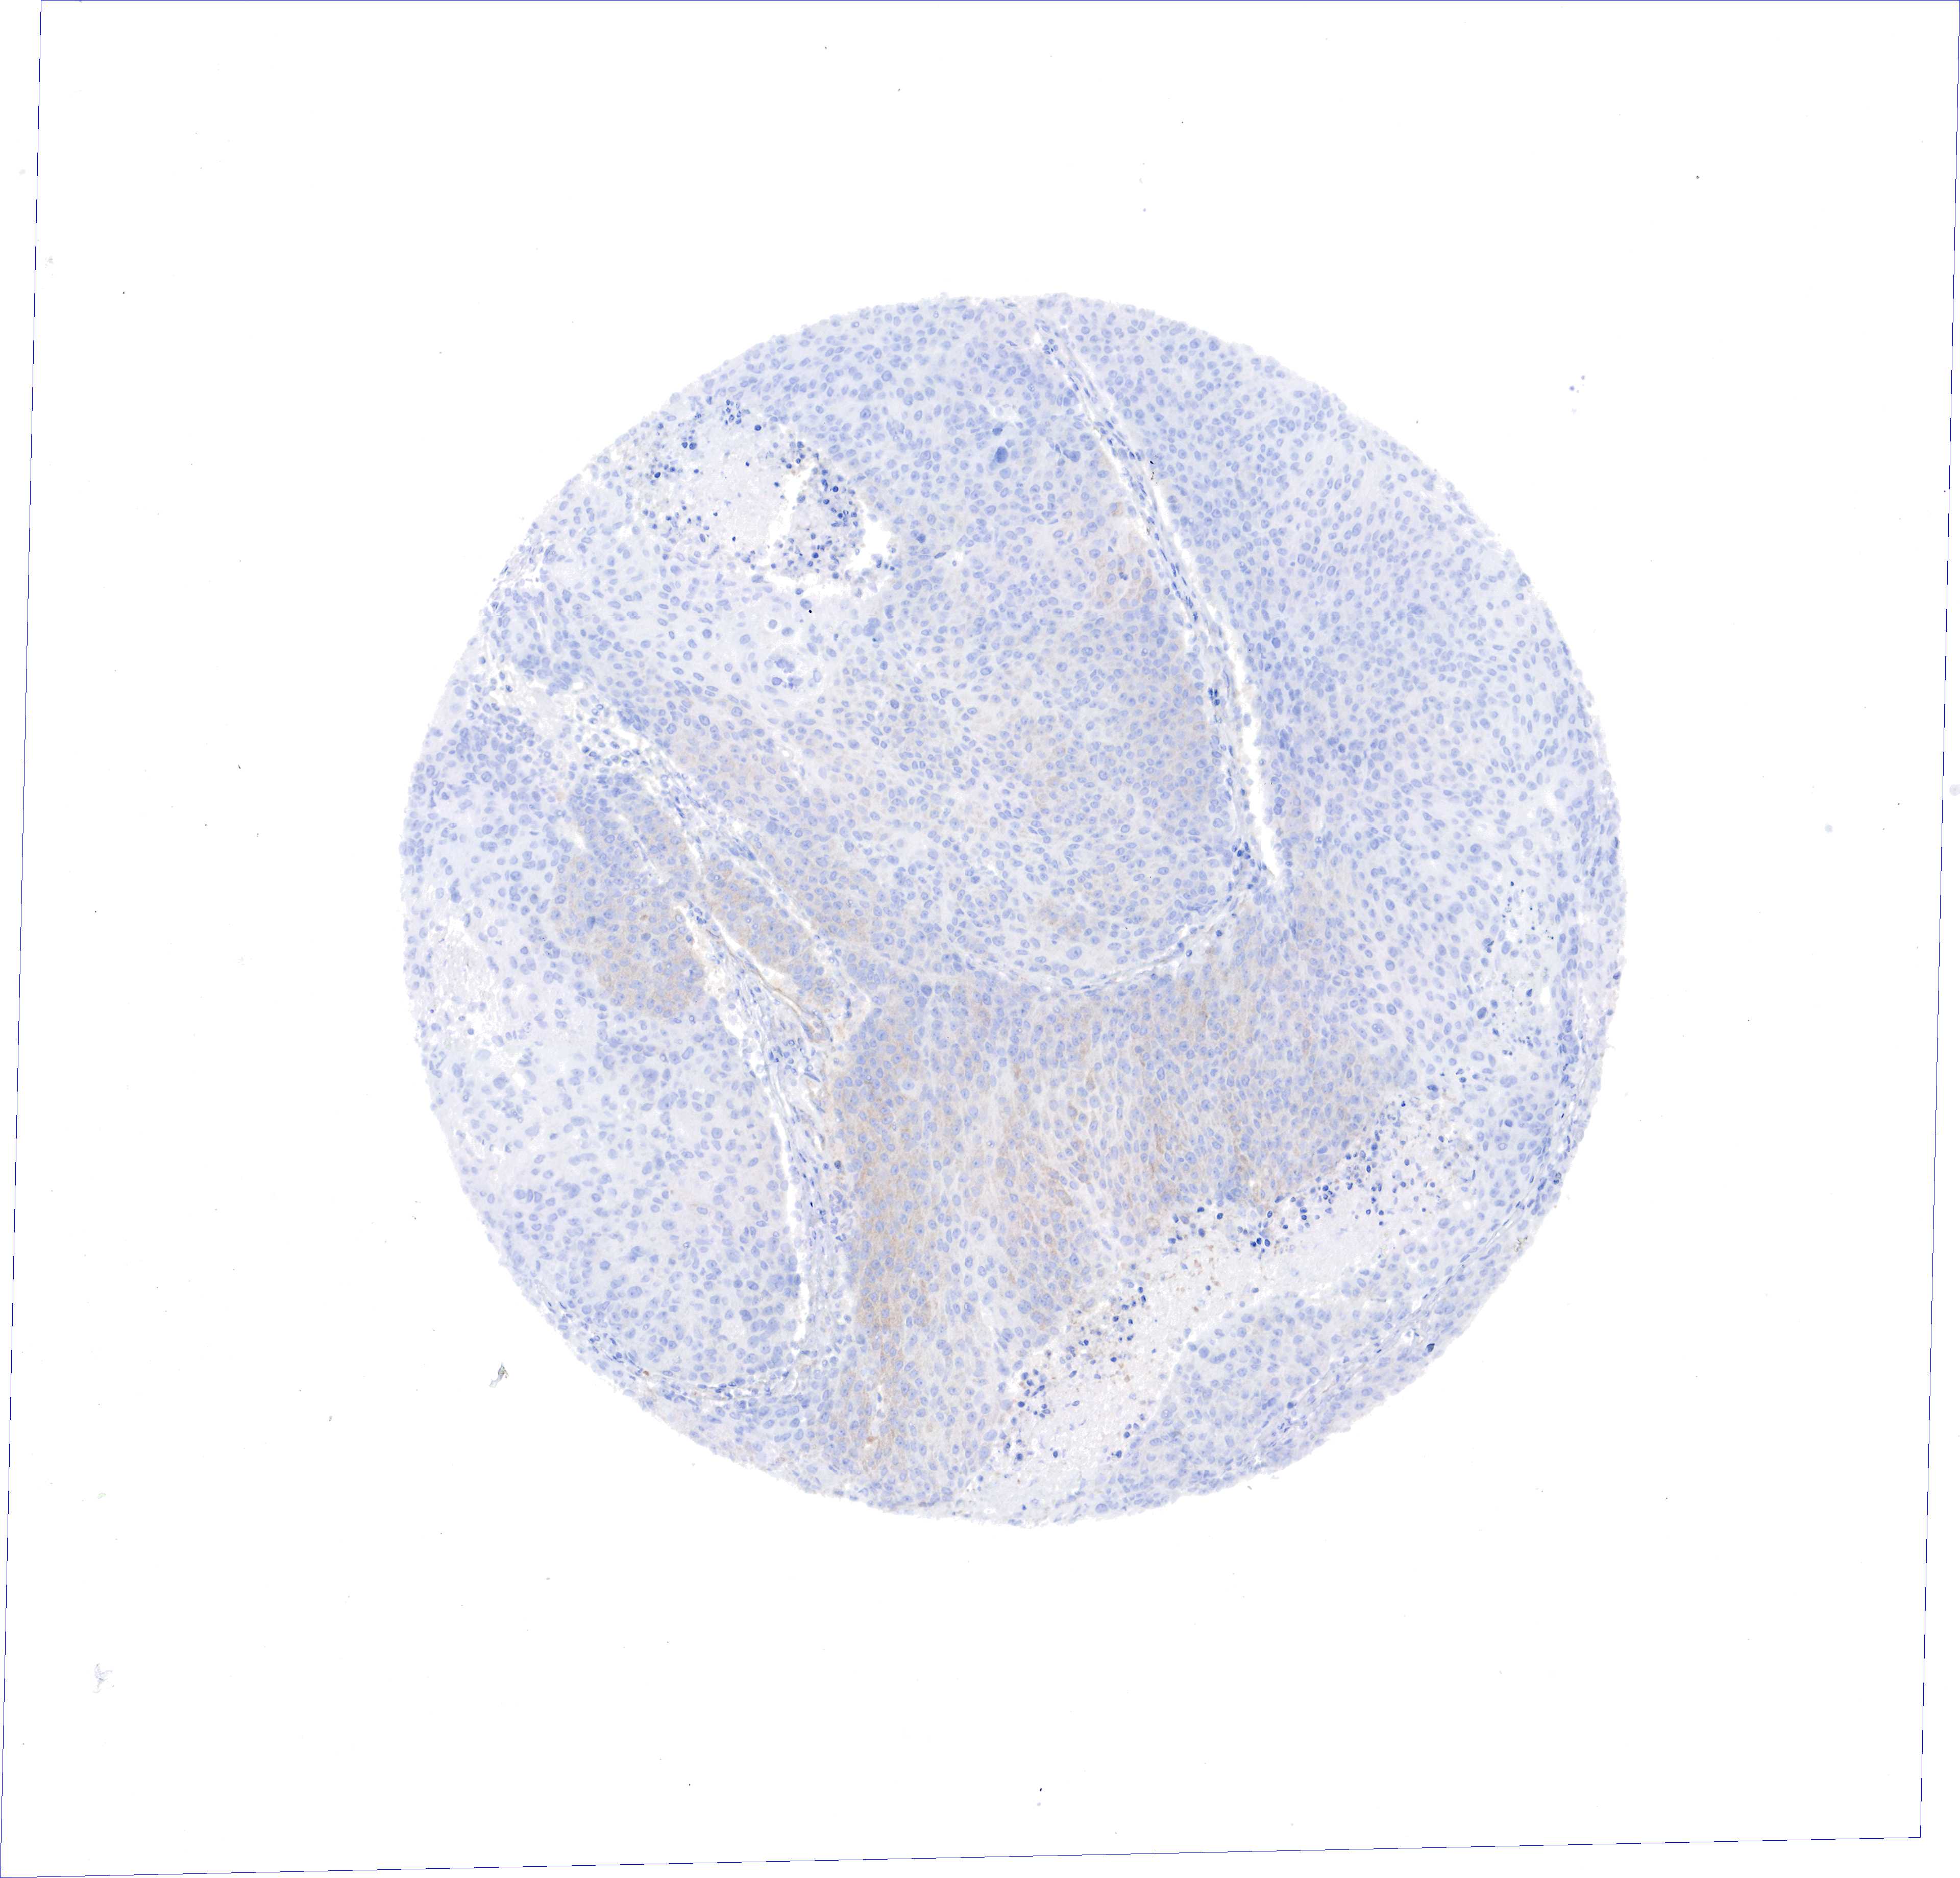

UROTHELIAL CANCER - Protein expressioni

A mouse-over function shows sample information and annotation data. Click on an image to view it in a full screen mode. Samples can be filtered based on level of antibody staining by selecting one or several of the following categories: high, medium, low and not detected. The assay and annotation is described here.

Antibody stainingi

Antibody staining in the annotated cell types in the current human tissue is reported as not detected, low, medium, or high, based on conventional immunohistochemistry profiling in selected tissues. This score is based on the combination of the staining intensity and fraction of stained cells.

Each image is clickable and will lead to virtual microscopy that enables deeper exploration of all samples and also displays staining intensity scores, fraction scores and subcellular localization as well as patient and tissue information for each sample.

Antibody HPA000263

Antibody HPA000763

Antibody CAB037312

Staining

High

Medium

Low

Not detected

Intensity

Strong

Moderate

Weak

Negative

Quantity

>75%

75%-25%

<25%

None

Location

Nuclear

Cytoplasmic/membranous

Cytoplasmic/membranous,nuclear

Urothelial carcinoma, High grade

Urothelial carcinoma, Low grade